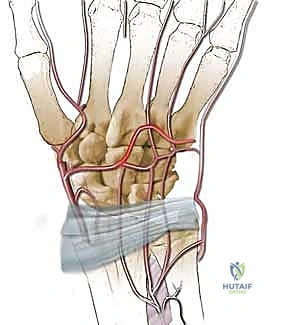

لفهم كيف يدمر مرض كينبوك مفصل الرسغ، يجب علينا أولاً أن نغوص في دقة وإعجاز التشريح البشري لهذا المفصل. يتكون الرسغ من ثمانية عظام صغيرة تُعرف بـ "عظام الرسغ" (Carpal Bones)، مرتبة في صفين (صف قريب وصف بعيد)، وترتبط ببعضها وبـ عظام الساعد (الكعبرة والزند) عبر شبكة معقدة من الأربطة القوية.

التروية الدموية: نقطة الضعف القاتلة

السبب الجذري لمرض كينبوك يكمن في التروية الدموية الفريدة (والهشة أحياناً) للعظم الهلالي. تتلقى معظم العظام الدم من عدة أوعية دموية تدخل من اتجاهات مختلفة. ومع ذلك، في حوالي 20% إلى 30% من البشر، يتلقى العظم الهلالي إمداده الدموي من وعاء دموي واحد فقط (Single Volar or Dorsal Artery). إذا تعرض هذا الوعاء الدموي الوحيد للانسداد، أو التمزق بسبب صدمة، أو الضغط المستمر، فإن العظم يُحرم من الأكسجين والمواد المغذية، مما يؤدي إلى بداية عملية النخر (موت الخلايا العظمية).

2. يتم تحديد قطعة صغيرة من العظم السليم من منطقة قريبة (غالباً من عظمة الكعبرة السفلية - Distal Radius).

3. الجزء الحاسم: لا يتم أخذ العظم فحسب، بل يتم استئصاله مع الشريان والوريد المتصلين به (Pedicled graft). هذا يعني أن قطعة العظم المنقولة لا تزال حية وتنبض بالدم.

5. يُزرع الطعم العظمي الحي (الوعائي) داخل التجويف الذي تم إنشاؤه في العظم الهلالي.

6. تعمل الأوعية الدموية المنقولة كـ "شريان حياة" جديد، حيث تبدأ في تغذية العظم الهلالي، مما يحفز الخلايا العظمية (Osteoblasts) على بناء نسيج عظمي جديد وقوي.